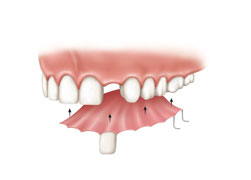

Utilizing dental implants to retain a complete denture is an excellent option to make it more functional and increase one’s confidence. There are a variety of options to do this, but adding just two implants to the mandibular denture is one of the the most popular and cost effective methods to gain more stability of the lower denture. By adding more implants you can improve stability and retention much like a four legged stool is more stable than balancing on just two legs. After the implants are secure to the bone, attachments called locator abutments are assembled between the denture and implants. These allow the denture to snap on to the implants. This still allows the patient to remove their dentures for easy cleaning, but helps eliminate the discomfort of them pressing on the tissues and embarrassment of the denture moving around while eating, talking, skydiving or laughing.

If patients are not enamored by either of these options and wish to abandon the concept of having a denture that comes in and out of their mouth, dental implants may also be used to retain a fixed prosthesis, one that is not removed by the patient and is bolted down and can only be removed by a dentist. In this scenario, four or more implants are placed in either arch, and prostheses are secured to them. Unlike dentures that rest on the gum tissue, a small amount of space is kept below the fixed prostheses to allow for better hygiene. A dentist is able to remove them if needed for repairs or more thorough cleanings.